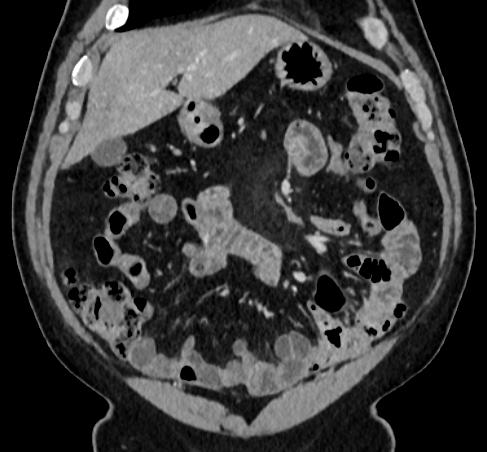

Over the years, there have been attempts to develop automatic methods for small bowel segmentation, especially using deep learning. The small bowel was included in segmenting multiple organs-at-risk for radiotherapy treatment planning of affected tissues, such as pancreatic and cervical cancers, in CT scans [8, 9, 13]. Although the results obtained for the small bowel are reasonable, some of their data included only the part of the small bowel that is closest to the target area, which needed to be dose-evaluated [8, 9]. In [13], the rough bowel location was detected instead of performing pixel-accurate small bowel segmentation. There have been only a few previous works dedicated solely to automatic small bowel segmentation [12, 14, 21]. While the specific anatomic relationship between the mesenteric vasculature and the small bowel is used to guide the small bowel segmentation in [21], a cylindrical shape constraint is applied during training of the small bowel segmenter in [14]. Although each of the works showed reasonable performance for particular datasets, their generalizability across different datasets was not evaluated. A CT scan is acquired using a specific imaging protocol depending on the purpose of the investigation, which includes the use of different contrast media and scan timing. Thus, the appearance of the small bowel may be different across datasets as exemplified in Figure 1. It is observed in our experiment that, when trained on one dataset, the model does not generalize well to another dataset due to the domain shift (section 3).

In this paper, we present a novel unsupervised domain adaptation method for small bowel segmentation, which is based on feature disentanglement. Although the absolute intensity values in CT scans (Hounsfield units) carry important information on specific substances of the human body, thus could provide a clue of being specific tissues and organs, they may be variable according to the imaging protocol. Figure 1 shows example CT scans that were acquired with and without oral contrast administration. The absolute intensity values are no longer a strong clue for the small bowel when we train and test across the datasets. Non-intensity features like texture and shape may be more useful. For example, local textures of the valvulae conniventes, which are circular folds on the inner surface of the small bowel, are more recurrent across the datasets.

A

B

B

C

C

D

D